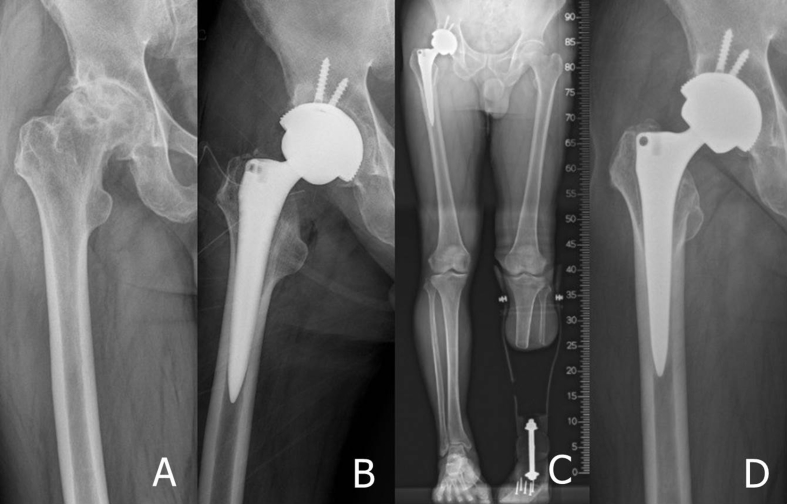

Fig. 1.

(A) Preoperative radiographs of a 67-old-year man with primary osteoarthritis of the hip joint. (B) Postoperative radiograph shows excellent implant position of cementless total hip arthroplasty. (C) Postoperative standing whole lower extremity radiographs taken of the prosthetic leg. (D) At 7 years after the operation, the radiograph shows stable fixation of components without subsidence or changes in alignment.